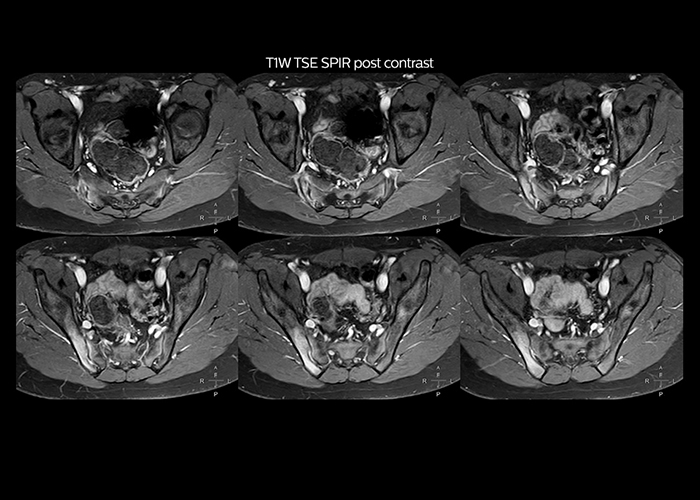

“Since we have Multiva, we have improved our workflow, because it has been so easy for our operators to learn and use Multiva. Our operators notice that the coils are lightweight and coils don’t need to be changed frequently. The user interface is easy to use. Features like this help us to scan a high number of patients. For instance, the musculoskeletal coils can be used interchangeably, and due to the user-friendly interface, the number of mistakes such as, for example, correct coil element selection has decreased significantly, because the system does it automatically by itself.” “Most important, Multiva satisfies our clinical imaging needs very well,” says Mr. Tuna. “Many features of Multiva have become similar to the Ingenia system. Even in more complex imaging such as abdominal and cardiac, the image quality and performance of Multiva is better than we expected. General surgeons and physicians from our hospital’s internal medicine department prefer to refer to us because of this.”